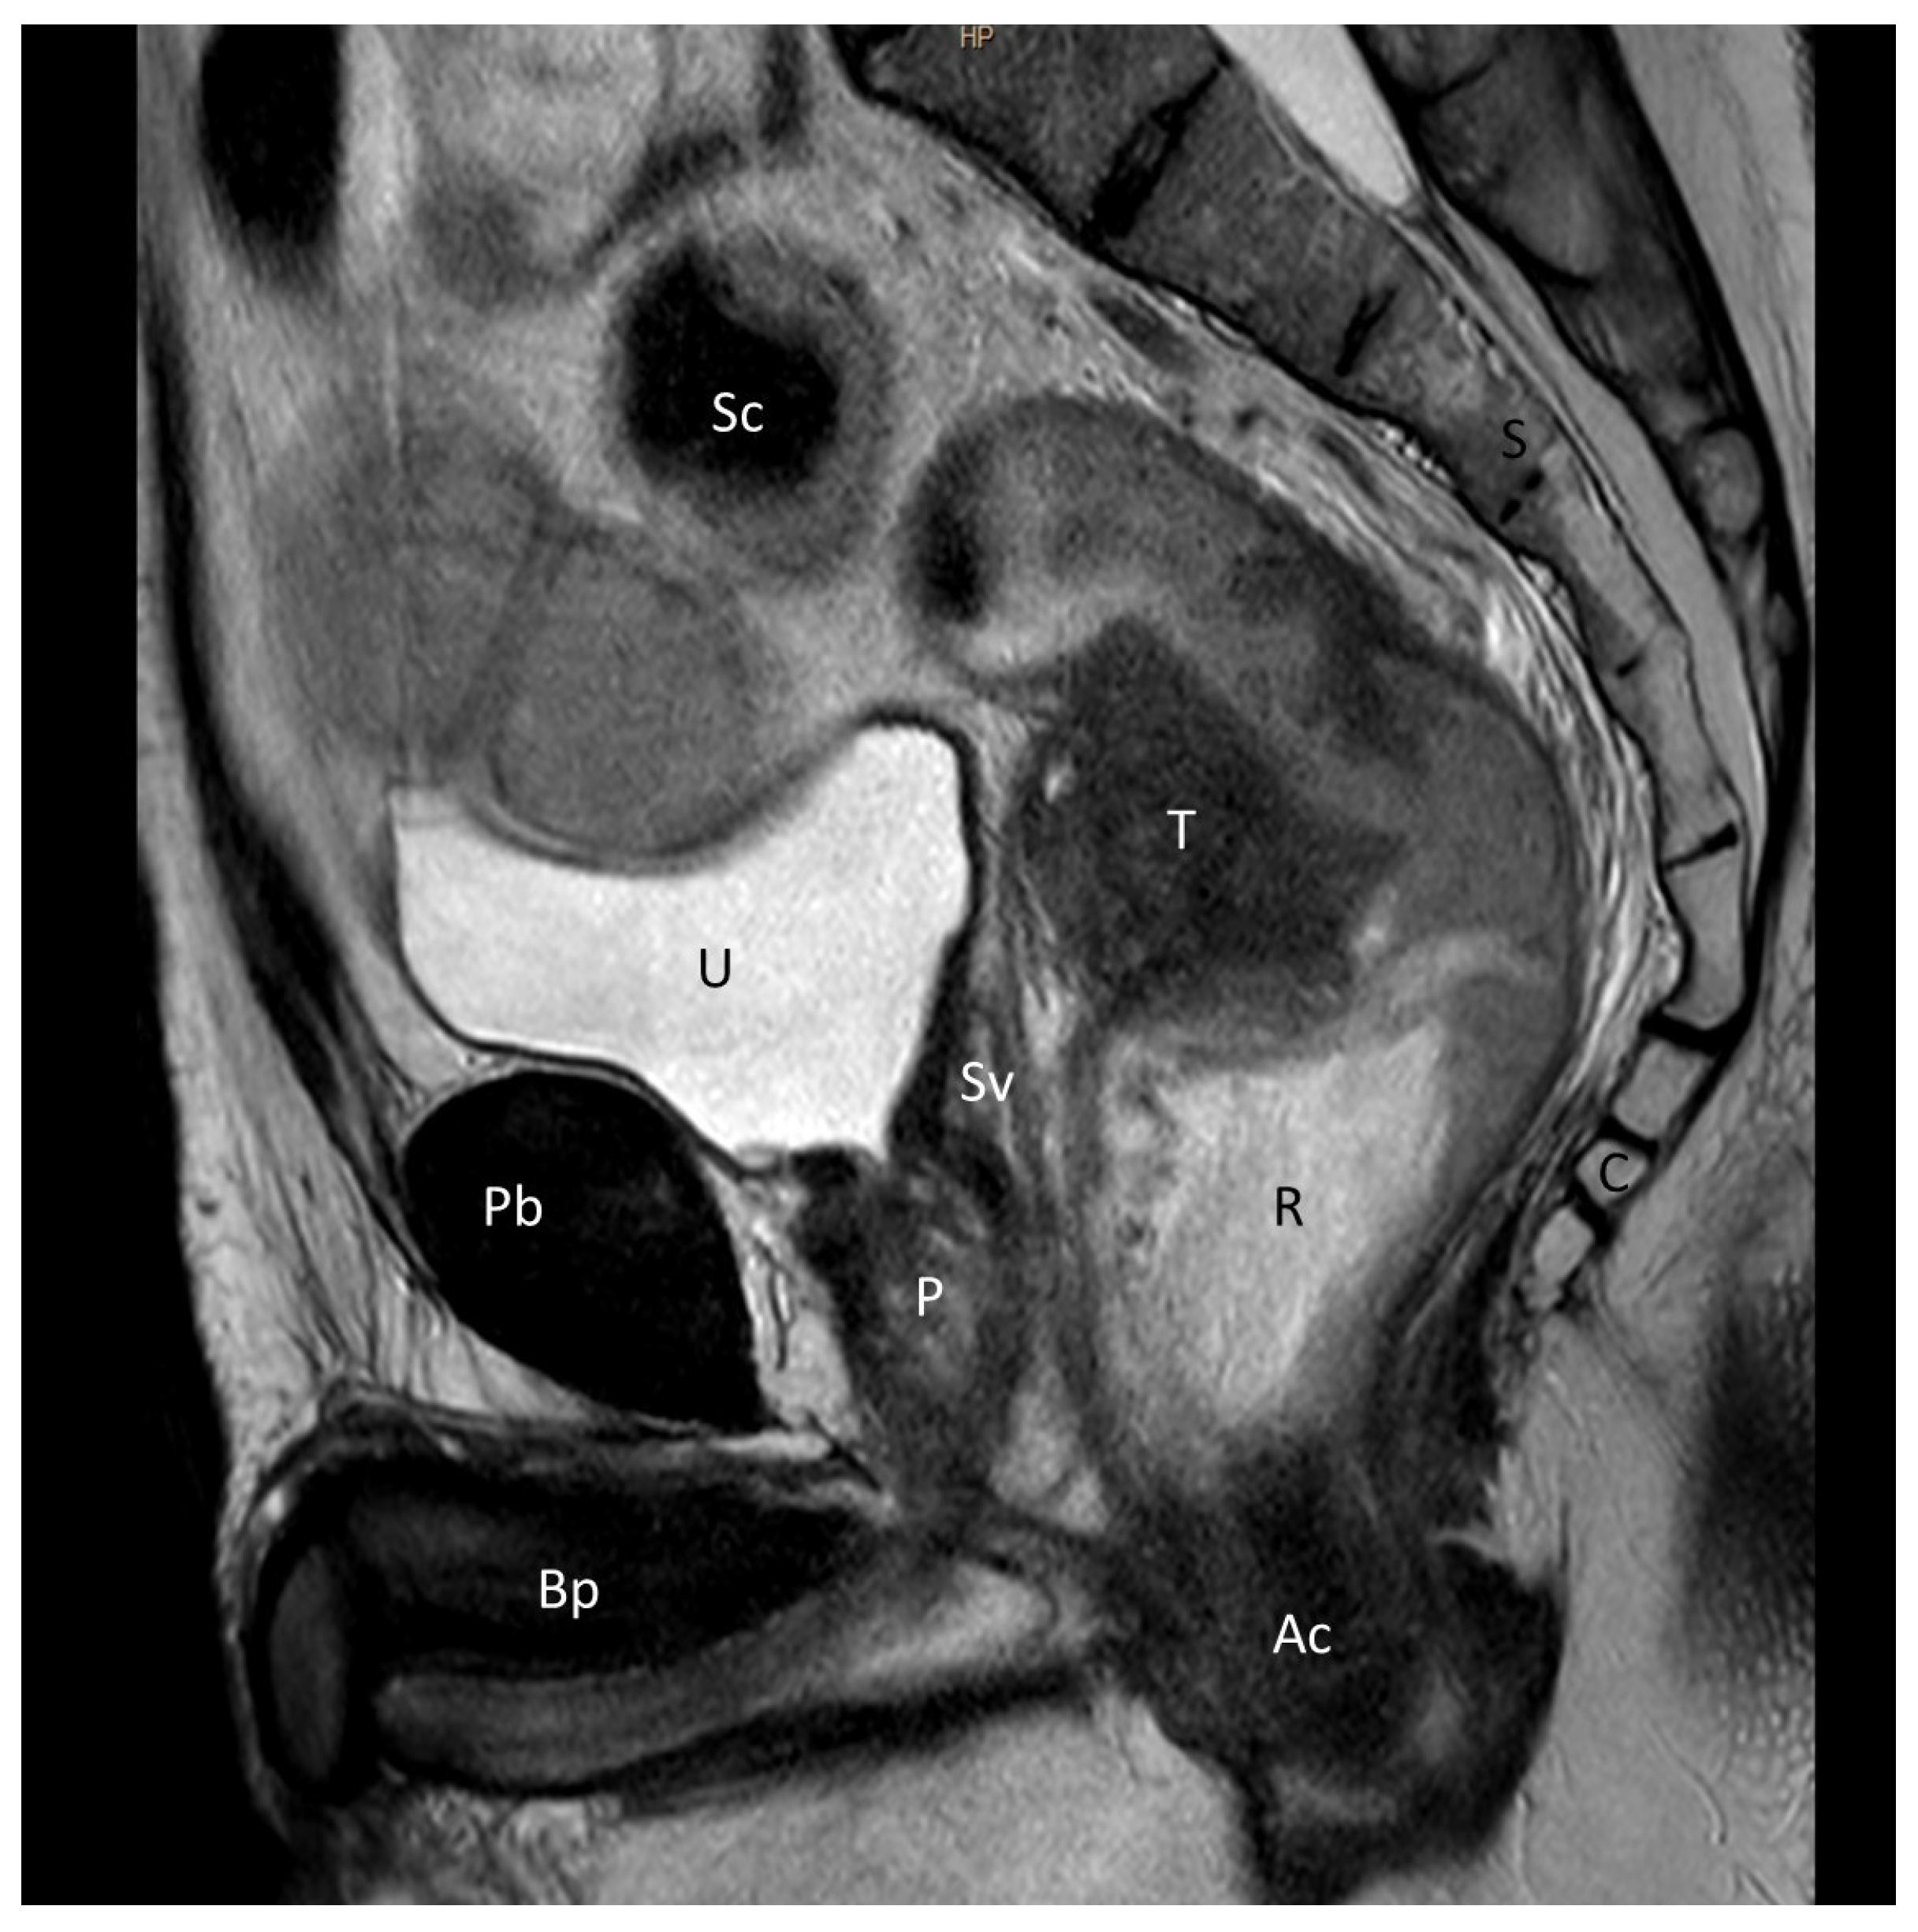

2.2. Anatomical Critical Point Description

- The shortest distance between the anterior surface of the rectum and the membranous urethra (R-Mu distance);

- The distance between the point on the anterior wall of the rectum closest to the membranous urethra and the anal margin (R-Am distance);

- The angle formed by the intersection of the axis of the anal canal and the axis of the rectum (anorectal angle).

3.2. Analysis of Imaging Studies